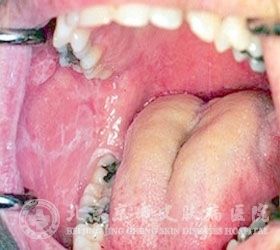

口腔扁平苔藓是如何得的?我们周围有很多人被口腔扁平苔藓所困扰,常常会问这个问题。但目前有很多患者对口腔扁平苔藓了解不足,错过了较佳治疗时机,从而导致病情发展严重。其实在日常生活中只要了解口腔扁平苔藓,就可以更早的发现以及治疗口腔扁平苔藓,从而降低给我们带来的影响。及时发现口腔扁平苔藓,及时治疗,才可以减少皮肤损伤。知道口腔扁平苔藓的原因,就可以及时预防口腔扁平苔藓。

北京京城皮肤医院指出,口腔扁平苔藓是一种慢性的炎症性皮肤病,其发病原因比较复杂,一般认为是受幽门螺杆菌的感染而发作,患者自身的微循环障碍因素、遗传因素等都是口腔扁平苔藓的发病原因。患者在日常的生活中如果能够尽量的减少这些危险因素的侵袭,就能在一定的程度上减少口腔扁平苔藓的发作。

口腔扁平苔藓的病因与患者的精神因素、内分泌因素、感染因素、因素因素等都是有着较大的关系的,患者日常一定要注意才会避免这些不适的出现。